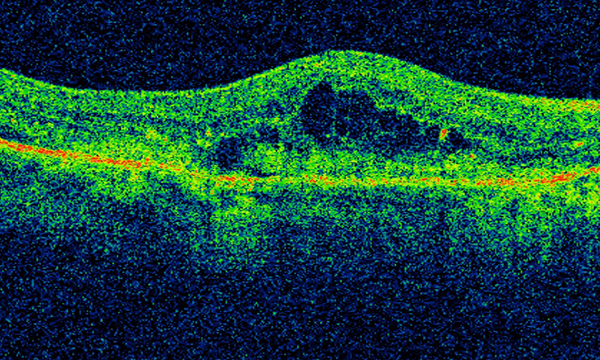

Aim The aim of this literature review was to explore the development of the role of specialist ophthalmic nurses in delivering ranibizumab intravitreal injections to patients with wet age-related macular degeneration (AMD), and to evaluate their contribution to reducing capacity pressures in medical retina services, while maintaining safe and effective standards of care.

Findings Five studies were identified from the literature search, which audited a total of 31,303 injections delivered by nurse practitioners between January 2007 and November 2013. The visual outcomes and the rate of complications from intravitreal injections delivered by trained ophthalmic nurse practitioners were comparable to intravitreal injections delivered by ophthalmologists. Four of the five studies reported increased patient satisfaction, patients consenting to nurse-delivered intravitreal injections, favourable pain experience, and absence of complaints.